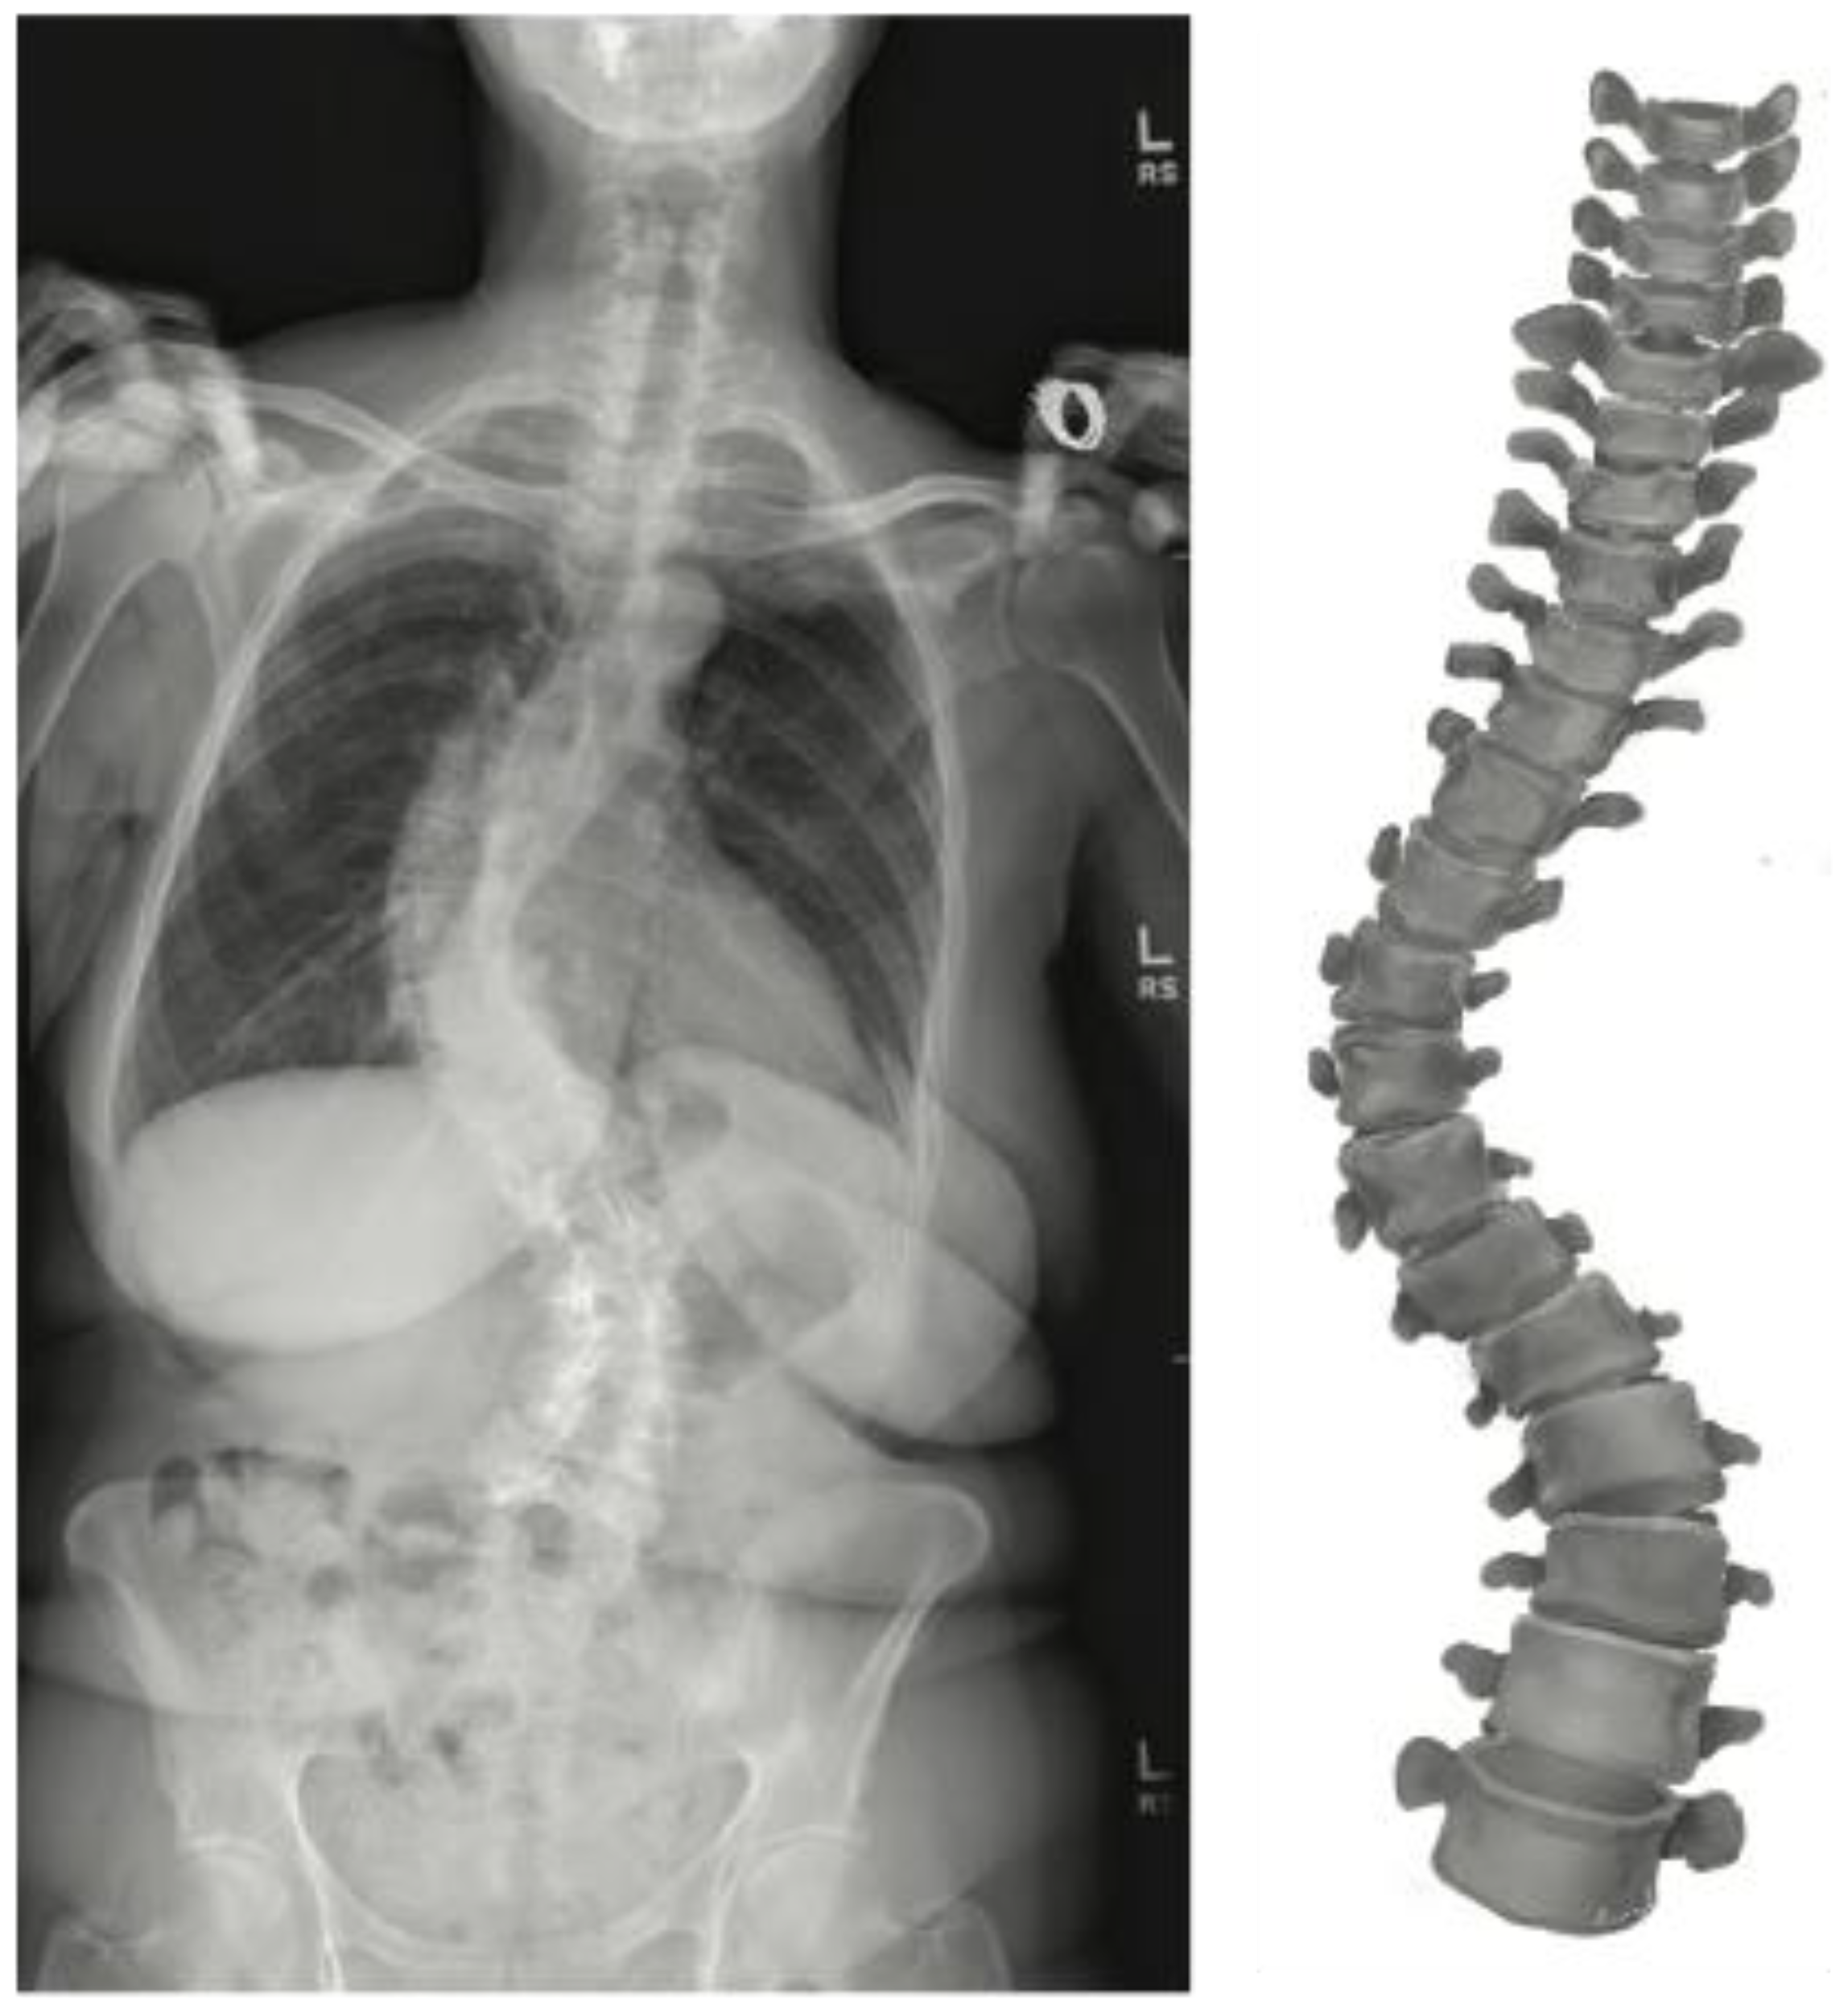

2.2. Pre-Operative Modeling